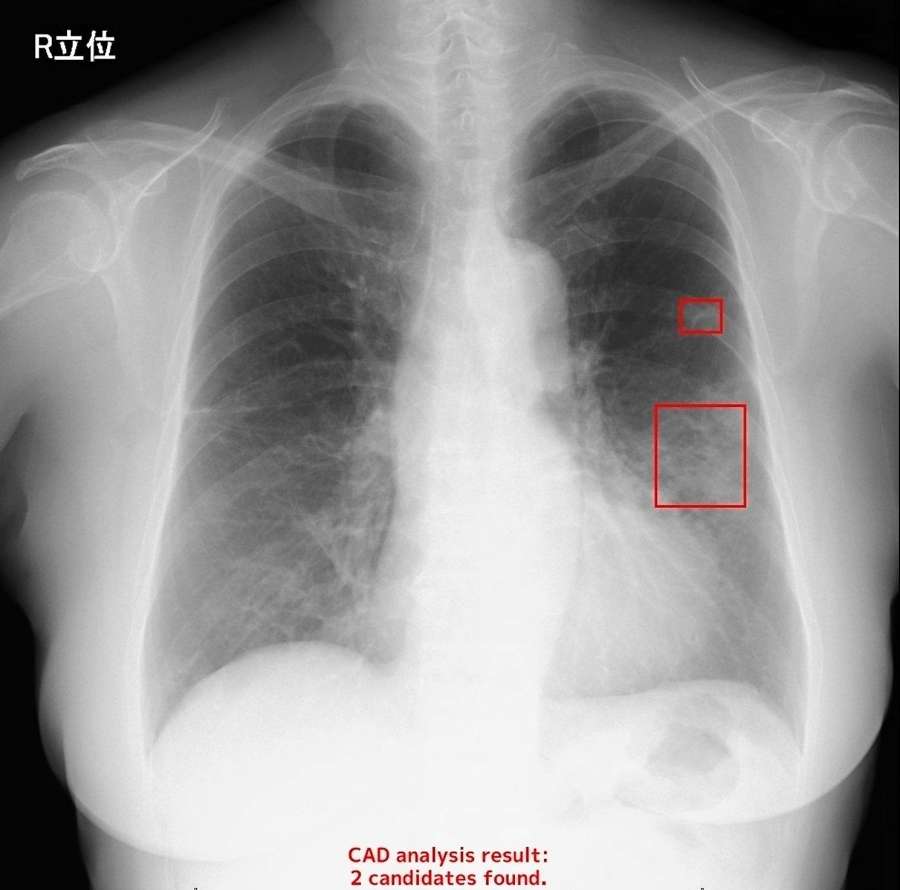

AIが胸部エックス線検査の画像を分析するイメージ。肺がんが疑われる部分が赤い四角で囲まれている(エルピクセル提供)

人工知能(AI)で画像分析し、がんなどの病変発見を手助けする医療機器が全国に広がりつつある。導入した鹿児島県内の医療機関からは、診断の見落とし防止や医師の心… [